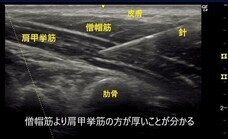

エコー検査によって、僧帽筋の厚さを測定することができます。20代の女性においては、筋盛り上がりのある部分で僧帽筋の厚さは約8mm程度であり、10mmを超えると厚く感じられます。(なお、僧帽筋の奥には、肩こりの原因とされる肩甲挙筋が存在し、その厚さは約5mm程度です。)

よくあるのですが、僧帽筋よりも肩甲挙筋の方が分厚いときなどはとくに当てはまります。